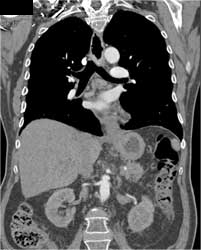

Carcinoma of the Gastric Fundus